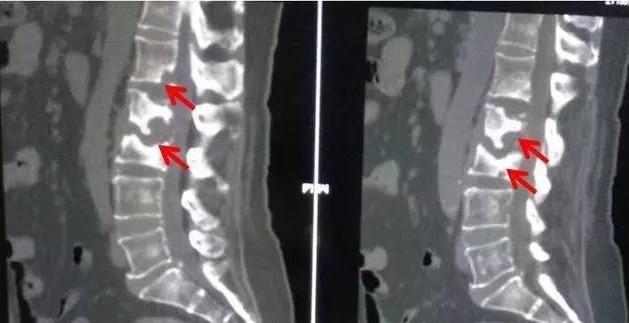

比如结核杆菌到我们的脊柱,就会产生脊柱结核。结核病灶会破坏患者的脊柱,导致患者出现腰背疼痛,驼背,严重的,甚至可以引起瘫痪。

被结核破坏的脊椎骨